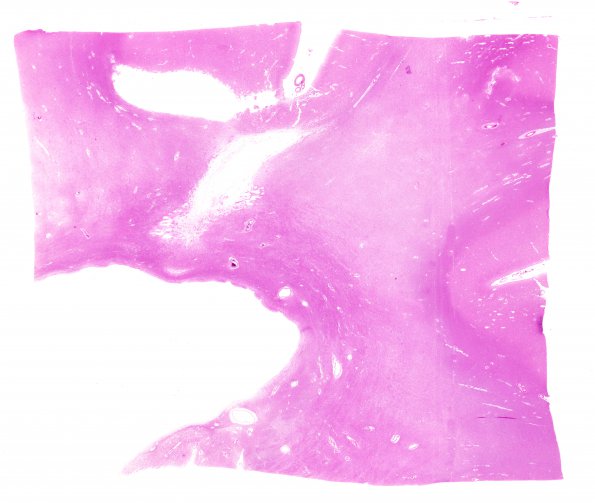

19B1 Atherosclerosis, DM & HT (Case 19) N14 H&E WM

19B1,2 In many areas of white matter there is pallor and myelin loss (H&E, LFB-PAS)